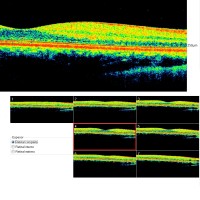

Tomografía de Coherencia óptica (OCT)

La tomografía de coherencia óptica, comúnmente conocida como OCT, es una técnica ecográfica de diagnóstico, control y seguimiento, que nos permite el estudio de cortes histológicos del ojo "en vivo". Fundamentalmente se utiliza para evaluar el estado de la parte central de la retina (mácula) y de la papila óptica (nervio óptico), aunque también se puede ver, entre otras estructuras la córnea, iris y el cristalino.

Estudio de la Papila Óptica (GDX y OCT de Nervio óptico)

Analiza la retina y crea un mapa detallando del grueso de la capa retiniana y fibras nerviosas de la retina central, en particular en la región que rodea el nervio óptico. La máquina proporciona, más allá de las mediciones de espesor real, también un análisis estadístico que indica el nivel de daño en cada área de la retina.